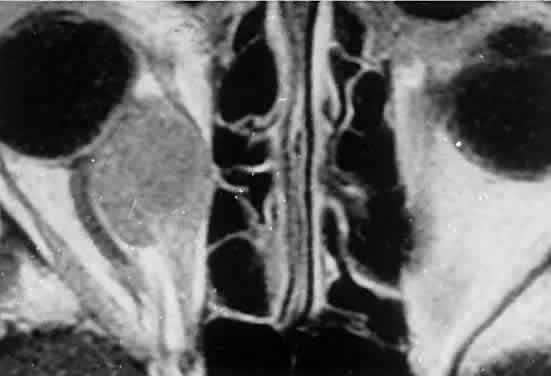

Acute blood cyst formation in this age group makes the distinction between a pre-existent but clinically silent lymphangioma and a rapidly emerging rhabdomyosarcoma a common orbital diagnostic problem. Evidence suggesting an orbitallymphangioma includes the variable finding of conjunctival or eyelid components of the malformation.86 Conjunctival lesions appear as ectatic channels filled with clear or hemorrhagic fluid. Eyelid ecchymosis may result from the seepage of blood out of the thin-walled orbital cysts. Additional developmental anomalies of the eye and adnexa may be present. Other head and neck involvement may be manifest as local hypertrophy (e.g., of the cheek or lips), and cystic palatal lesions may be seen. CT discloses a single or multilobulated mass, which represents only the blood cyst portion of the tumor (Fig. 14). Individual lobules may have different radiodensities depending on the presence of clots or liquefied blood within each cyst (Fig. 15). A generalized increase in orbital dimensions suggests a long-standing, probably congenital process. Echography may help differentiate the cystic components of lymphangioma from cellular rhabdomyosarcoma. Echography shows the blood cysts to be acoustically inactive spaces, with extremely low internal reflectivity (Fig. 16). Clots within the cysts can increase internal heterogeneity, however. MRI has virtually eliminated the need for diagnostic biopsy in this condition, because of its ability to show differing magnetic properties of suspended, degrading blood products (Fig. 17).